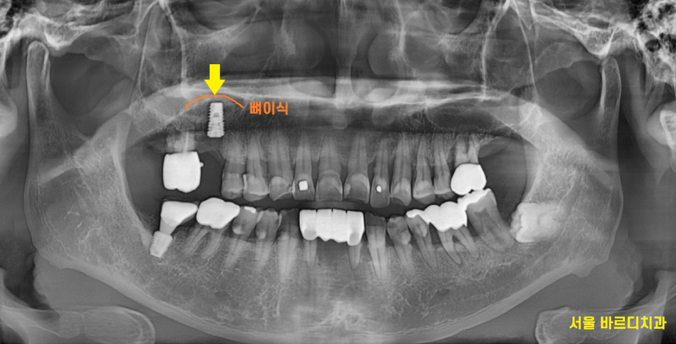

230708

우선 상황이 안좋긴 하지만

가장 불편함을 호소하신 치아 1개만 제거

임플란트를 시행하였습니다.

231118

다른 안좋은 치아들은

관리하면서 최대한 잇몸 무너지는 것을 방지하기로 계획해드렸습니다.

강일동 임플란트가 완성되기까지

다른 부위 잇몸치료도 진행해드리고

염증 치료를 시행하였습니다.